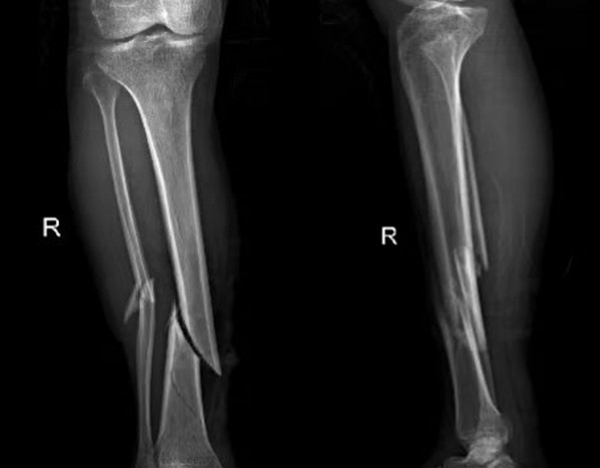

比如外傷患者,排查有無(wú)四肢骨折,X光片是首選,因?yàn)樗芸焖偾逦@示骨骼的連續(xù)性;而檢查關(guān)節(jié)內(nèi)的軟組織(如韌帶、半月板),則需要靠MRI,CT對(duì)此幾乎“無(wú)能為力”。所以,別主動(dòng)要求“升級(jí)”檢查,聽從醫(yī)生的專業(yè)建議,才能既準(zhǔn)確又高效。